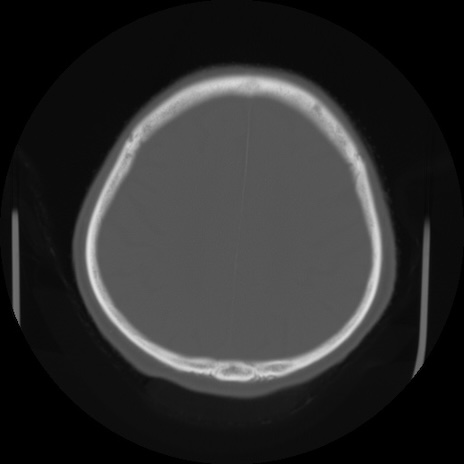

【頭部】症例5 CT(横断像)

症例5の画像所見と診断は?